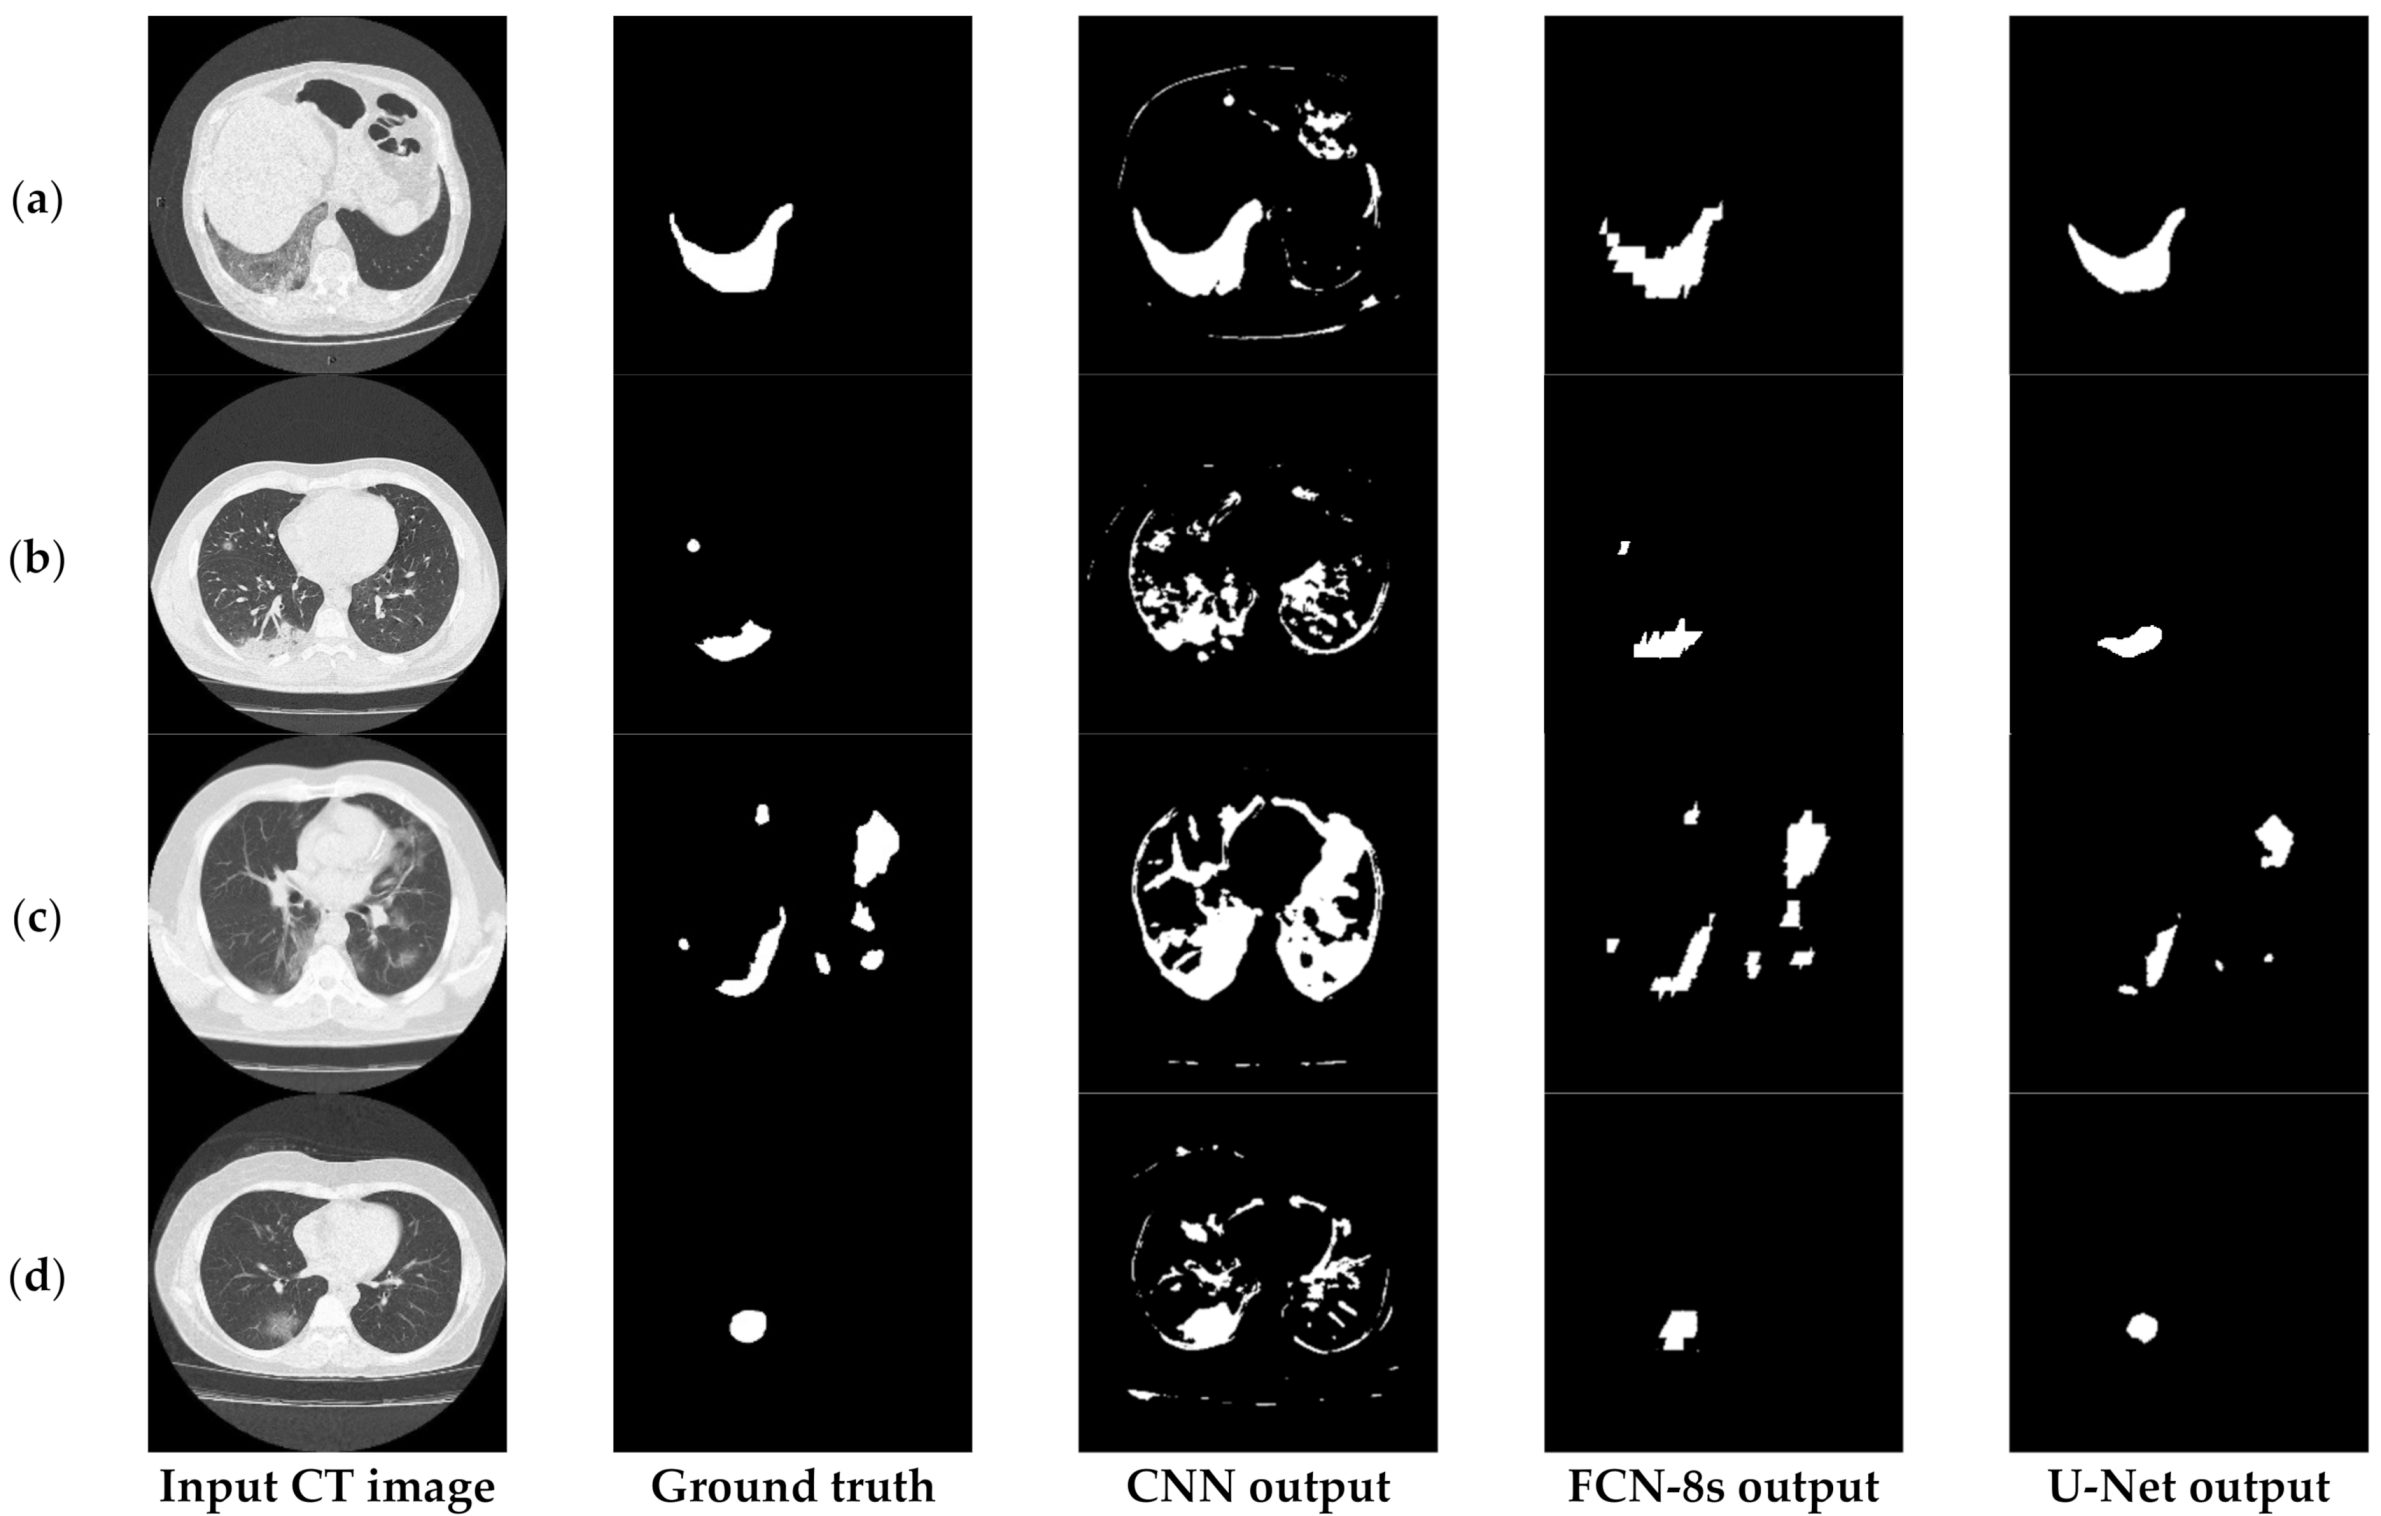

6.3.2. The Performance of the Proposed Few-Shot U-Net Model